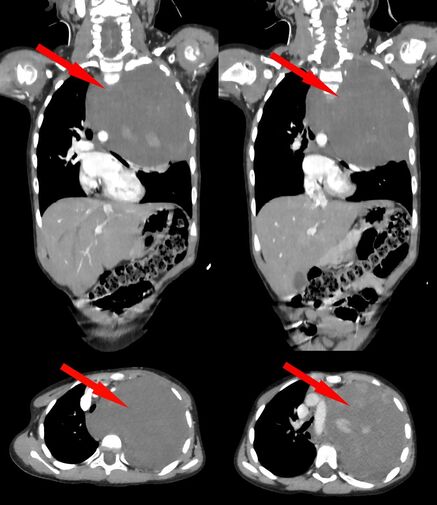

Родители показали дочь врачам, когда заметили у нее небольшую припухлость в области шеи. Специалисты по месту жительства выявили огромное новообразование размером со страусиное яйцо, которое сдавливало сердце и легкое. Сквозь ткань опухоли проходили крупные сосуды: «позвоночная артерия, питающая головной мозг, и подключичная артерия с ее ветвями, питающая левую руку». После телемедицинской консультации ребенка направили в Москву.

«Учитывая гигантский размер опухоли и ее расположение вблизи множества жизненно важных структур, мы использовали расширенный доступ по типу «раковины моллюска». Он предполагает рассечение не только межреберного промежутка, но и самой грудины, что позволяет «раскрыть» грудную клетку, как раковину», — рассказал заведующий отделением реконструктивной и восстановительной хирургии грудной полости РДКБ, к.м.н. Евгений Андреев об операции.

«По результатам контрольного гистологического исследования всего объема опухоли были обнаружены злокачественные клетки и установлен точный диагноз — ганглионейробластома», — поделились в пресс-службе.